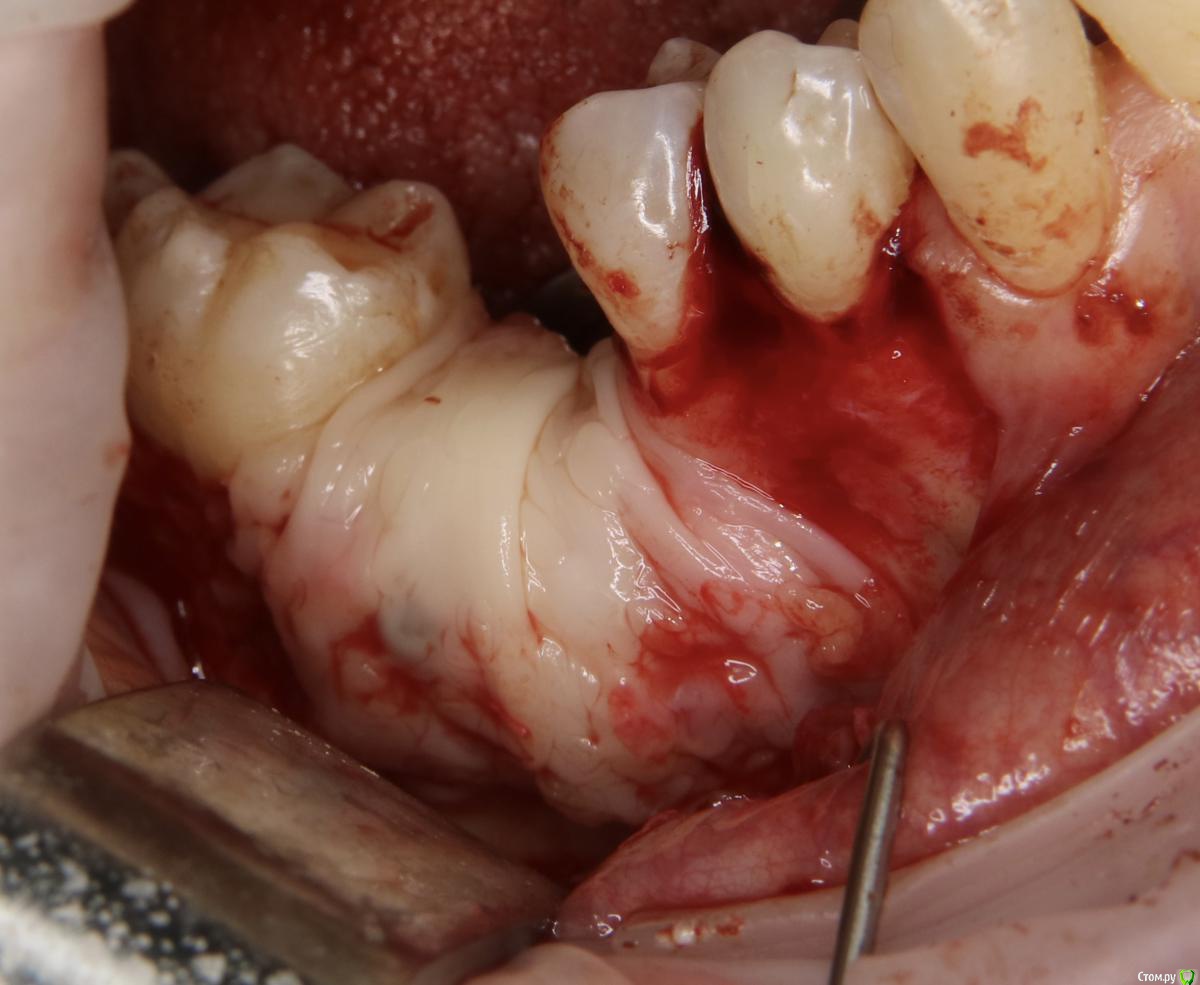

Александр07 Опубликовано 21 августа, 2020 Поделиться Опубликовано 21 августа, 2020 Коллеги добрый день, решил углубиться в тематику костных пластин по Кюри, определенные знания и некоторый опыт есть, небольшой, хотел поделиться последней работой, если какие то советы /замечания есть с удовольствием выслушаю 8 Ссылка на комментарий

Bier Опубликовано 21 августа, 2020 Поделиться Опубликовано 21 августа, 2020 толстый очень ламинат. а так все хорошо ) Ссылка на комментарий